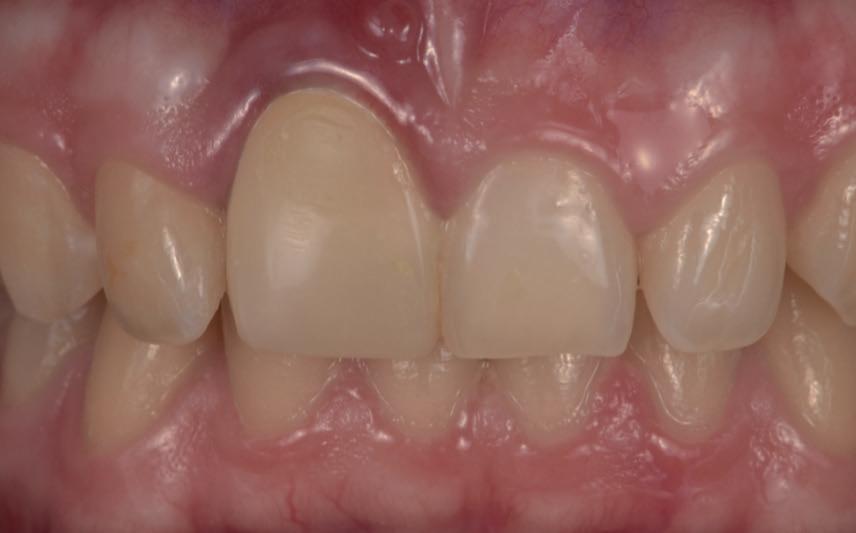

Je kan nu denken, heb ik nu net een gans artikel gelezen van een endodontoloog over hoe ik vooral geen wortelkanaalbehandelingen moet doen? Iemand die zo tegen zijn winkel spreekt kan waarschijnlijk gewoon geen goede wortelkanaalbehandelingen uitvoeren… Deze opmerking heb ik al een aantal keren gehoord wanneer ik een presentatie geef. Meestal begin ik dan ook met het tonen van een zeer uitdagende casus. In dit geval zal ik hetzelfde doen. Foto 1 is een recente wortelkanaalbehandeling die ik uitgevoerd heb. Zowat de natte droom van elke endodontoloog. Nu dat van de baan is, nog enkele voorbeelden uit de praktijk waarbij ik de patiënt centraal heb gezet en soms tegen de vraag van de verwijzende tandarts ben ingegaan.

De verwijzende tandarts wil tanden 24 en 25 overkronen en vraagt evaluatie en eventuele wortel-

kanaalbehandelingen en stiftopbouwen (foto 2). U ziet, mijn verwijzers zijn getraind en vragen eerst een evaluatie of het wel nodig is. Dit heeft me bloed, zweet en tranen gekost, alsook enkele verwijzers. Uiteindelijk bleek tand 24 vitaal te zijn en was er voldoende restweefsel om adhesief te werken. De wortelkanaalbehandeling op de 25 is misschien technisch niet ideaal, maar er zijn geen klachten of radiologische tekenen van infectie. In overleg met de patiënt is dus besloten om tand 24 te voorzien van een stompopbouw en tand 25 van een glasvezelstift en stompopbouw zonder te herbehandelen (foto 3). De tandarts kan onmiddellijk verder met de kronen.